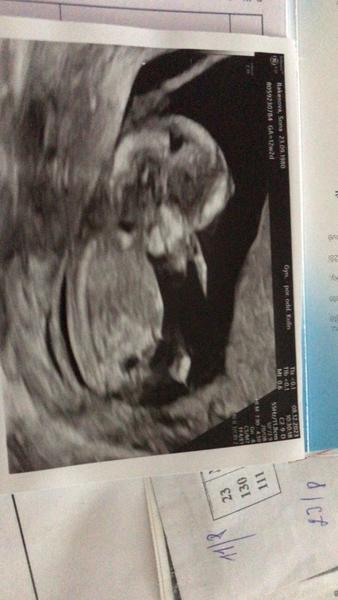

Dobrý den, oživuji diskuzi ❤️ 11tt, je to jen screenshot z videa které jsem si natočila na mobil, tak bůh ví, zda jsem to cvakla v dobrou chvíli a není to klamavé 😄 Co myslíte? Do prenatalu jdeme až 6.11. a já mám pocit že prasknu nedočkavostí, jsem zvědavec hrozný 🙈 Toť otázka - pohlavní hrbolek, nebo jsou to kulky, nebo konec kostrče? Co myslíte, jen tak pro srandu? Přáli bychom si holku, ale kdyz jsem videla prvni pohyby na UTZ v 11+1, tak jsem si uvědomila že ať bude co bude, budu mimi milovat uplne stejne bez rozdílu ❤️ Je to mazec!!

@veronka_123 No, včera jsem valila na pohotovost pro jistotu, nezdálo se vse jak by melo (nakonec vse OK). A pan doktor se pta: Uz vam rekli co to bude? Rikam ze ne, ze se to snad dozvíme az 6.11. na prenatalu. A on se tak uchechtl a říká: tak to já vám nic říkat nebudu… Takže si myslím, že tam viděl plápolat pinďu jak poleno 😀 Člověk míní, život mění. Tak nějak tusim, že z vytoužené holčičky bude kluk jako buk